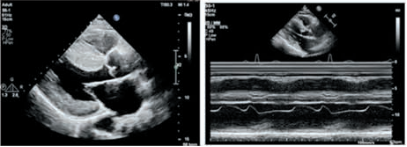

目標導向Valsalva

設備

操作過程